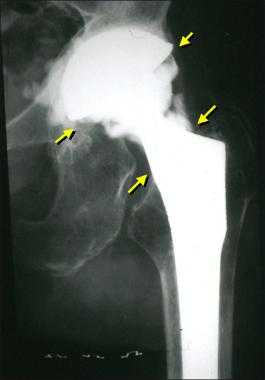

Парапротезная инфекция

Второе по частоте явление, характеризующееся активизацией тяжелых гнойно-воспалительных процессов в районе установленного имплантата. Инфекционные антигены заносятся интраоперационно через недостаточно стерильные хирургические инструменты (редко) или после вмешательства по кровеносному руслу перемещаются от любого проблемного органа, имеющего болезнетворно-микробную среду (часто). Плохая обработка раневой зоны или слабое заживление (при диабете) также способствует развитию и размножению бактерий.

Гнойный очаг пагубно воздействует на прочность фиксации эндопротеза, вызывая его расшатывание и нестабильность. Гноеродная микрофлора трудно поддается лечению и, как правило, предполагает снятие имплантата и проведение повторной установки спустя продолжительное время. Основный принцип лечения - тест на установление вида инфекции, долгая антибиотикотерапия, обильный лаваж раны антисептическими растворами.

Стрелками указаны зоны инфекционного воспаления, именно так они выглядят на рентгене.